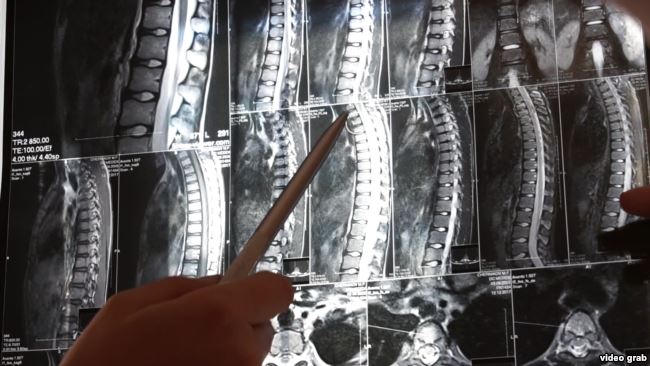

У лікарні хлопчикові зробили МРТ, де стало зрозуміло, що у Максима - перелом двох хребців.